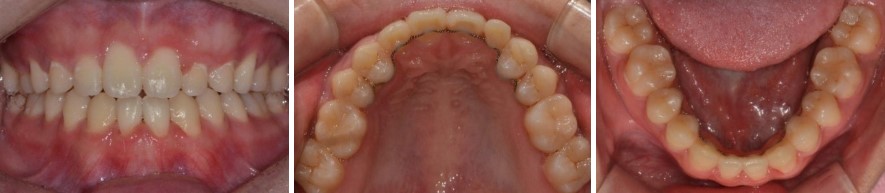

케이스 소개: 만 14세 남아, 선천적 결손치 + 개방교합 + 돌출입

이번 환자분은 만 14세 남학생이었습니다.

진단명

• 상악 양측 견치

• 하악 양측 중절치의 선천적 결손

• 전치부 개방교합

• 골격성 2급 부정교합

문제점

• 4개 치아의 선천적 결손

• 앞니가 잘 닿지 않는 전치부 개방교합

• 돌출입

• 상악 좌측 측절치(앞니 옆 치아)의 왜소치

747569ca512315b293293d02a0866f62_1763604888_1991.jpg

이미 보완해야 할 요소가 상당히 많은, 복합적인 케이스였습니다.